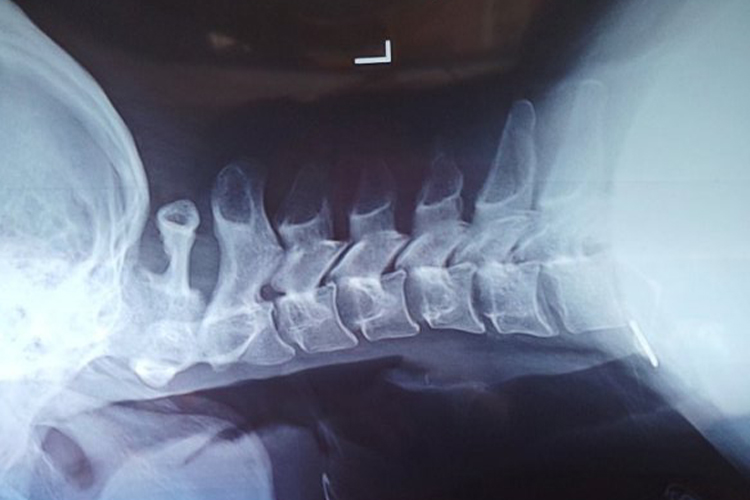

颈椎病患者侧面观时,可见生理前凸消失,甚至可呈后凸畸形,椎间隙狭窄,椎体前、后缘有唇样骨赘,椎体半脱位等改变。